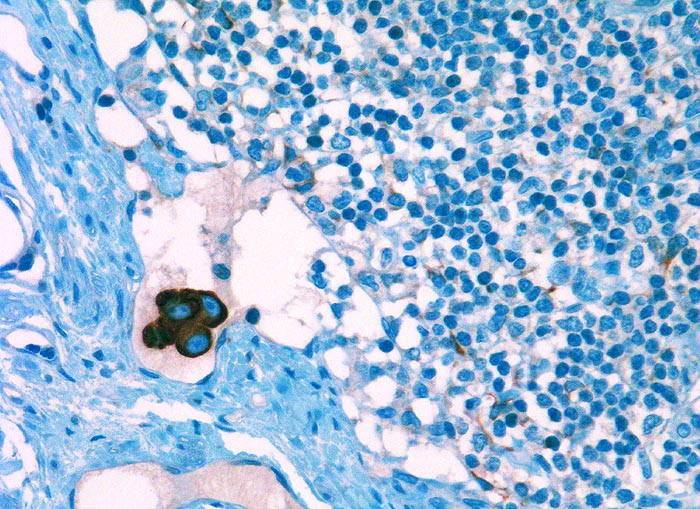

l/ Panzytokeratin (CK22/Lu-5)

Panzytokeratin (CK22/Lu-5)

Anfärbung:

Zytoplasma positiv.

Diagnostischer Nutzen:

Suchantikörper zur Abgrenzung von Karzinomen von Lymphomen, Sarkomen und malignen Melanomen. Identifikation von Karzinommikrometastasen in Lymphknoten.